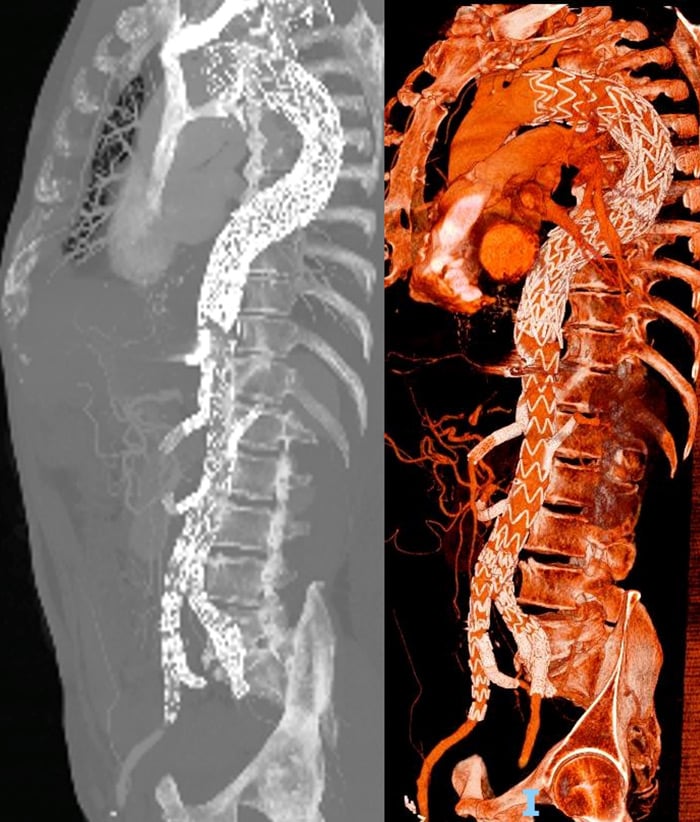

To limit the risk of spinal cord ischemia, a staged endovascular strategy was planned, combining TEVAR, a branched endograft with visceral vessel stenting, and bilateral iliac branch repair.

Due to the extension of the disease, to reduce the risk of spinal cord ischemia, we planned a multistage procedure:

- TEVAR (thoracic endovascular aortic repair)

- Deployment of a T-branch endograft with left renal artery and superior mesenteric artery stenting

- Bilateral iliac branch

- Stenting of right renal artery and celiac trunk